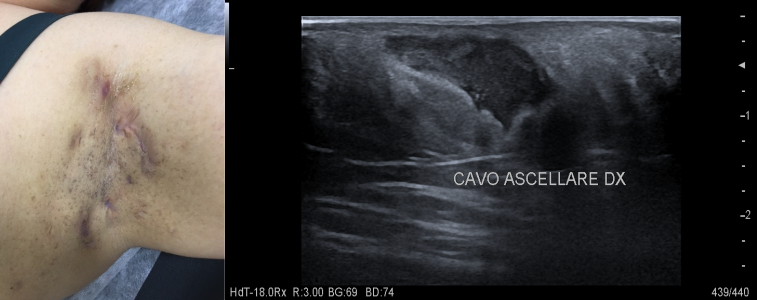

4. LINFOMI CUTANEI

Recidiva linfoma B cutaneo: all’ecografia aumento dello spessore dermo-epidermico e marcata vacolarizzazione. Componente Hard all’esame elastosonografico.